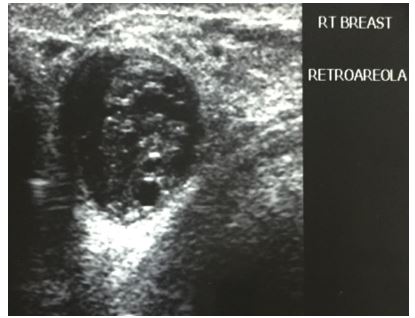

Singh et al [11]. reported a 24-year-old lady who had presented with a right-sided painless, palpable, cystic lump in the breast which was superior to the nipple within the retro-areolar region for 6 months, which was surgically excised. On examination Singh et al. [11] did find a linear incision mark over the right breast of the patient which was superior to her nipple (see figure 1).

She had pre-operative ultrasound scan of the breast which showed a round hypo-echoic lesion (see figure 2). Histopathology examination of the excised specimen showed a cyst that contained folds of laminated chitinous layer which was partly lining the wall of the cyst and the encompassing areas did show chronic inflammation with sheets of foamy macrophages (see figures 3 and 4). The microscopic examination of the specimen also showed foreign body giant cell reaction as well as occasional ill-formed granuloma and the surrounding normal breast tissue was also visualised (see figures 5 and 6). She was sent for further treatment.